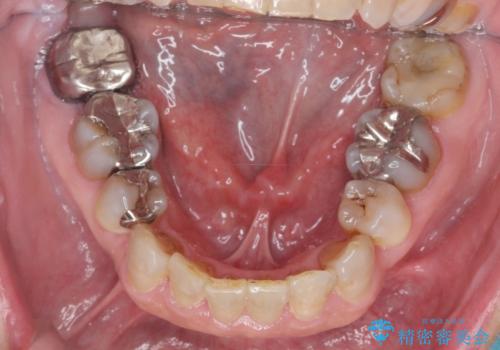

- 50代女性

- 1年6ヶ月

- ぐらぐらする歯や銀歯、なんとなくにおいのする奥歯の治療を求めて来院されました。

X線、歯周組織検査の結果、全体的に奥歯には重度〜中等度の歯周病の問題が見られました。

残すことのできない歯、予後の悪い歯を抜去し、ブリッジイ・ンプラントによる機能回復をおこなっていくと同時に、残すことのできる歯には歯周病治療をしっかりと行い、

将来に渡りしっかりと自分の歯で噛めるような口腔内環境を構築していきます。